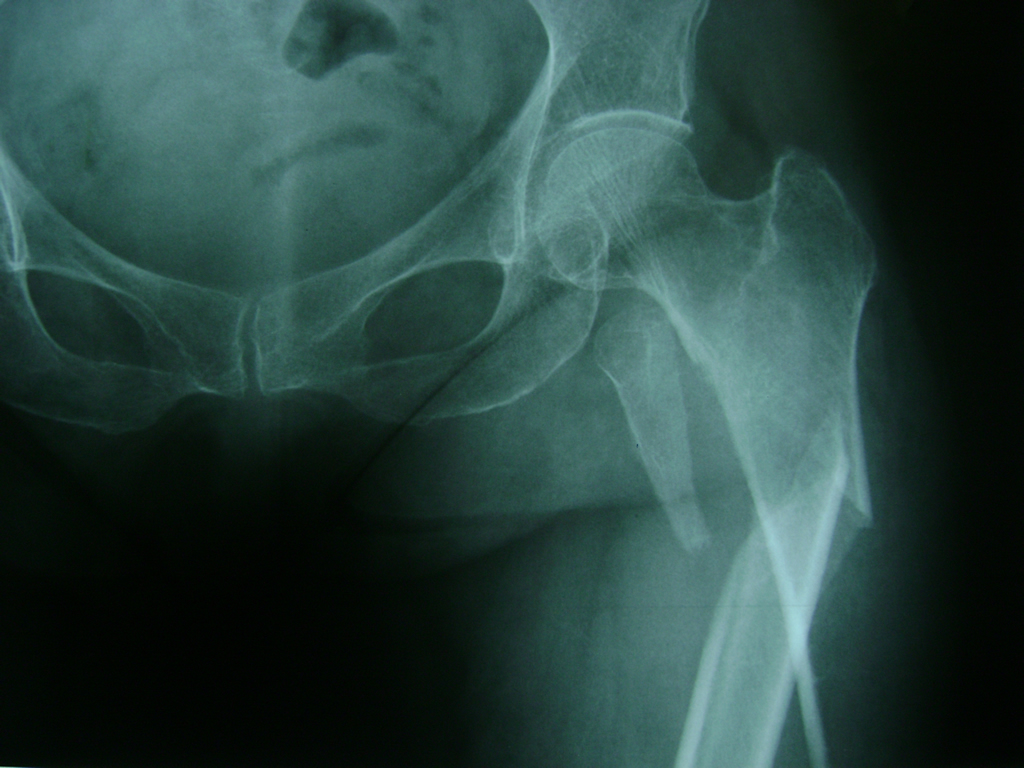

Cirugía de Fémur - Cadera

La cirugía de fractura de cadera se realiza para reparar una ruptura en la parte superior del hueso del muslo. Este hueso se denomina fémur.

Es parte de la articulación coxofemoral. Si una fractura de cadera no recibe tratamiento, es posible que deba permanecer en una silla o en la cama.